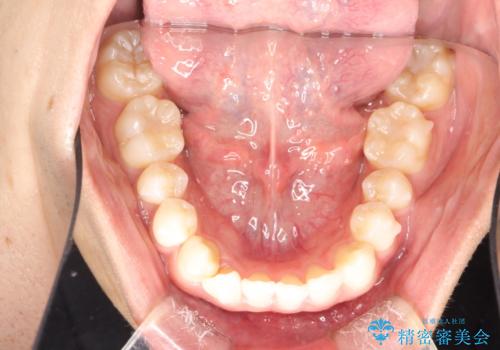

インビザラインによる矯正治療(非抜歯) 下の前歯の歯並びの改善

- 主に下の歯並びの改善を主訴としてご来院されました。

右下の犬歯と前歯が大幅に重なっているのと、歯の向きも大きく横に倒れています。この部位の正常な配列のためには、3次元的に大幅な移動が必要となりました。

マウスピース枚数 初回35枚 + 追加13枚

概ね1年弱で治療が完了しました。

前歯の大きな3次元的移動を可能にするために、当院独自の工夫を随所に盛り込み、狙い通りの治療結果を得られました。